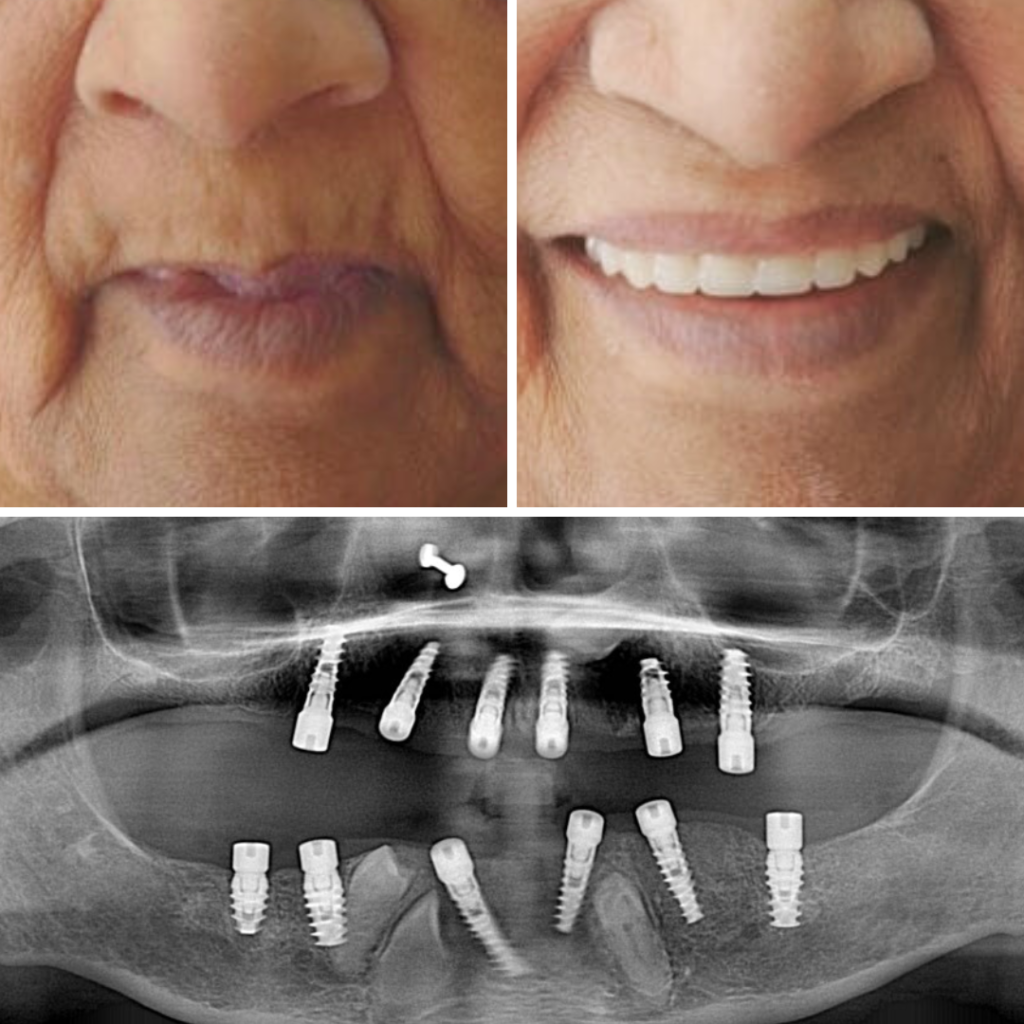

Real transformations. Real patients. Designed with precision and executed with clinical excellence.

Every treatment plan is guided by advanced diagnostics, digital planning tools and globally accepted implant systems — ensuring predictable, long-term results with uncompromising safety.

With 15+ years of clinical experience in advanced implantology and aesthetic dentistry, our approach blends science, symmetry and precision craftsmanship — ensuring every smile is both functional and beautiful.